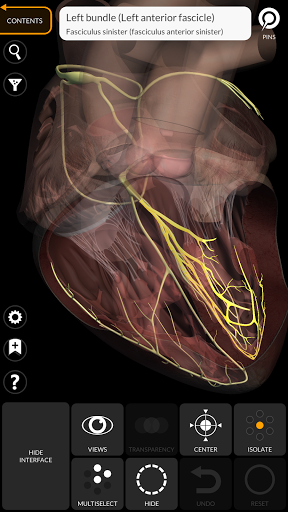

Grâce à une interface simple et intuitive, il est possible d'observer chaque structure anatomique sous n'importe quel angle.

Les modèles anatomiques 3D sont particulièrement détaillés et avec des textures jusqu'à une résolution de 4k.

• Système nerveux

• Option pour masquer ou isoler un ou plusieurs modèles sélectionnés

• Fonction de transparence

• En sélectionnant un modèle ou une épingle, le terme anatomique associé apparaît